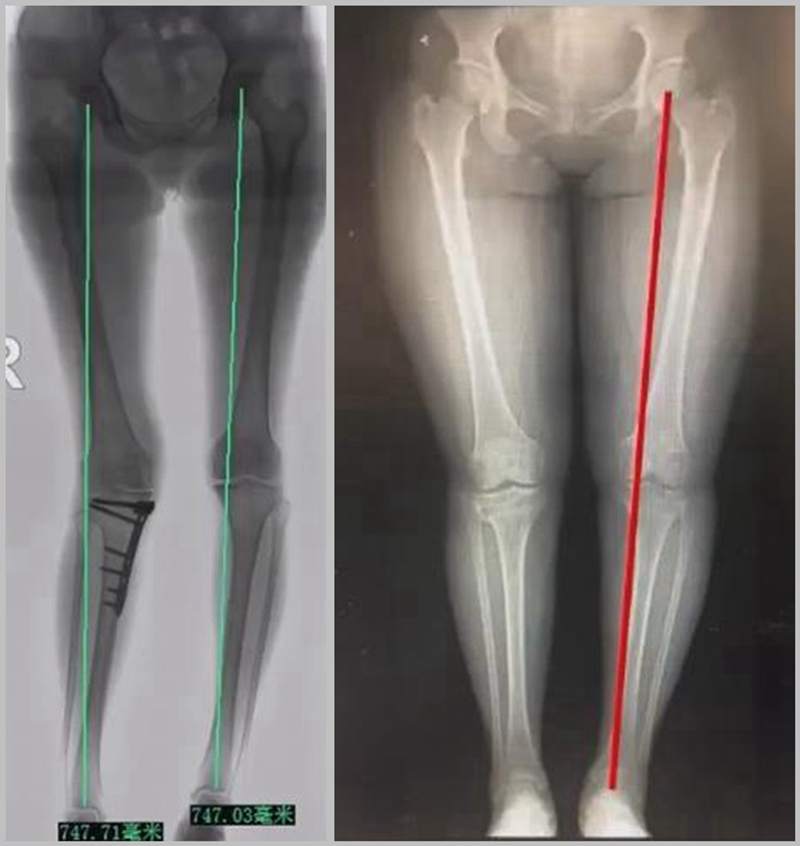

1、综合判断力线的方法

现在对于力线的判断大致通过以下几方面:①大体形态;②透视确定力线,连接股骨头中心、踝关节中心,看力线杆和膝关节中心的位置关系;③MPTA(胫骨平台关节线和胫骨侧机械轴夹角);④PSI。

(1)肢体外旋

一般来说在麻醉状态下肢体会处于外旋位,此时去测定力线的话往往需要将肢体放在旋转中立位,但是在内旋肢体的过程中会出现内翻应力,那么这种情况下判断力线会带来误差,所以通常建议大家要把手术床做一点旋转,让患肢处于自然的旋转中立位,这样再去判断力线就比较准确。

(3)力线验证未模仿负重应力

现在所谓的目标力线应该是模仿负重时的力线。做截骨时,通常会将力线轻度外移,如果没有考虑关节内畸形、韧带松弛或是软骨磨损,那么在负重时,在内侧副韧带撑开过程中,会出现力线偏移。所以要注意,手术中间在调整目标力线时,要以应力状态下为标准。